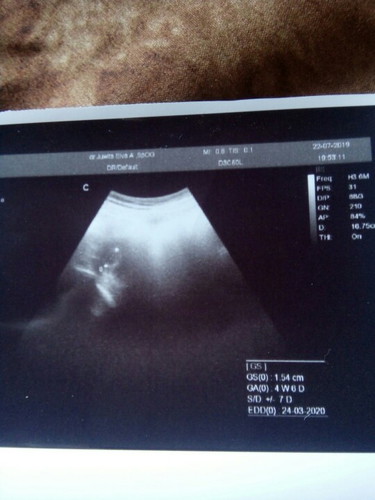

Bund ada yg sma kyk aku tp trnyta dd.y baik" ajj.. Aku prkiraan hamil tu 8wk.. Ps ush baru 4w6d... Bantu jwb bund.... Nngu 2mg lg.. Klo gk ada perkembangan mau d pksa keluar ??

Hitungan usg terkadanh berbeda bun dgn itungan kita, positif thinking dan banyak berdoa kpd Allah semoga janik baik2 dan sehat2. Memang kalo usia 4w blm terlihat bun, semoga 2 minggu nanti bunda balik kontrol lg sudah ada janin dan terdengar denyut jantung janin ya bun, semangat dan jg mikir macem2😉

Mens nya bunda teratur atau gak teratur bunda... Klw mens gk teratur emang suka gtu... Gak sama hasil usg n hpht.... Soalnya klw mens gak teratur kn untuk nentuin masa subur sulit.... Beda lg sama yg mens teratur siklus 28 hari itu bnyak cocok nya

Kayanya kalo di usg dilihat dari besar janinnya bun jd perhitungan mesin usg sama perhitungan hpht berbeda gitu